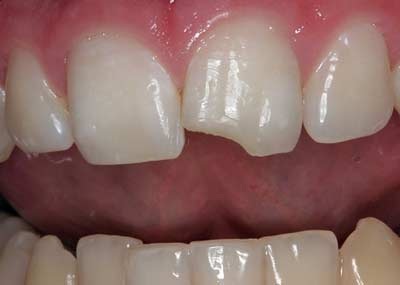

Không phải mọi răng bị vỡ đều cần được điều trị nhưng tốt nhất là nên đi khám để được tư vấn tốt nhất